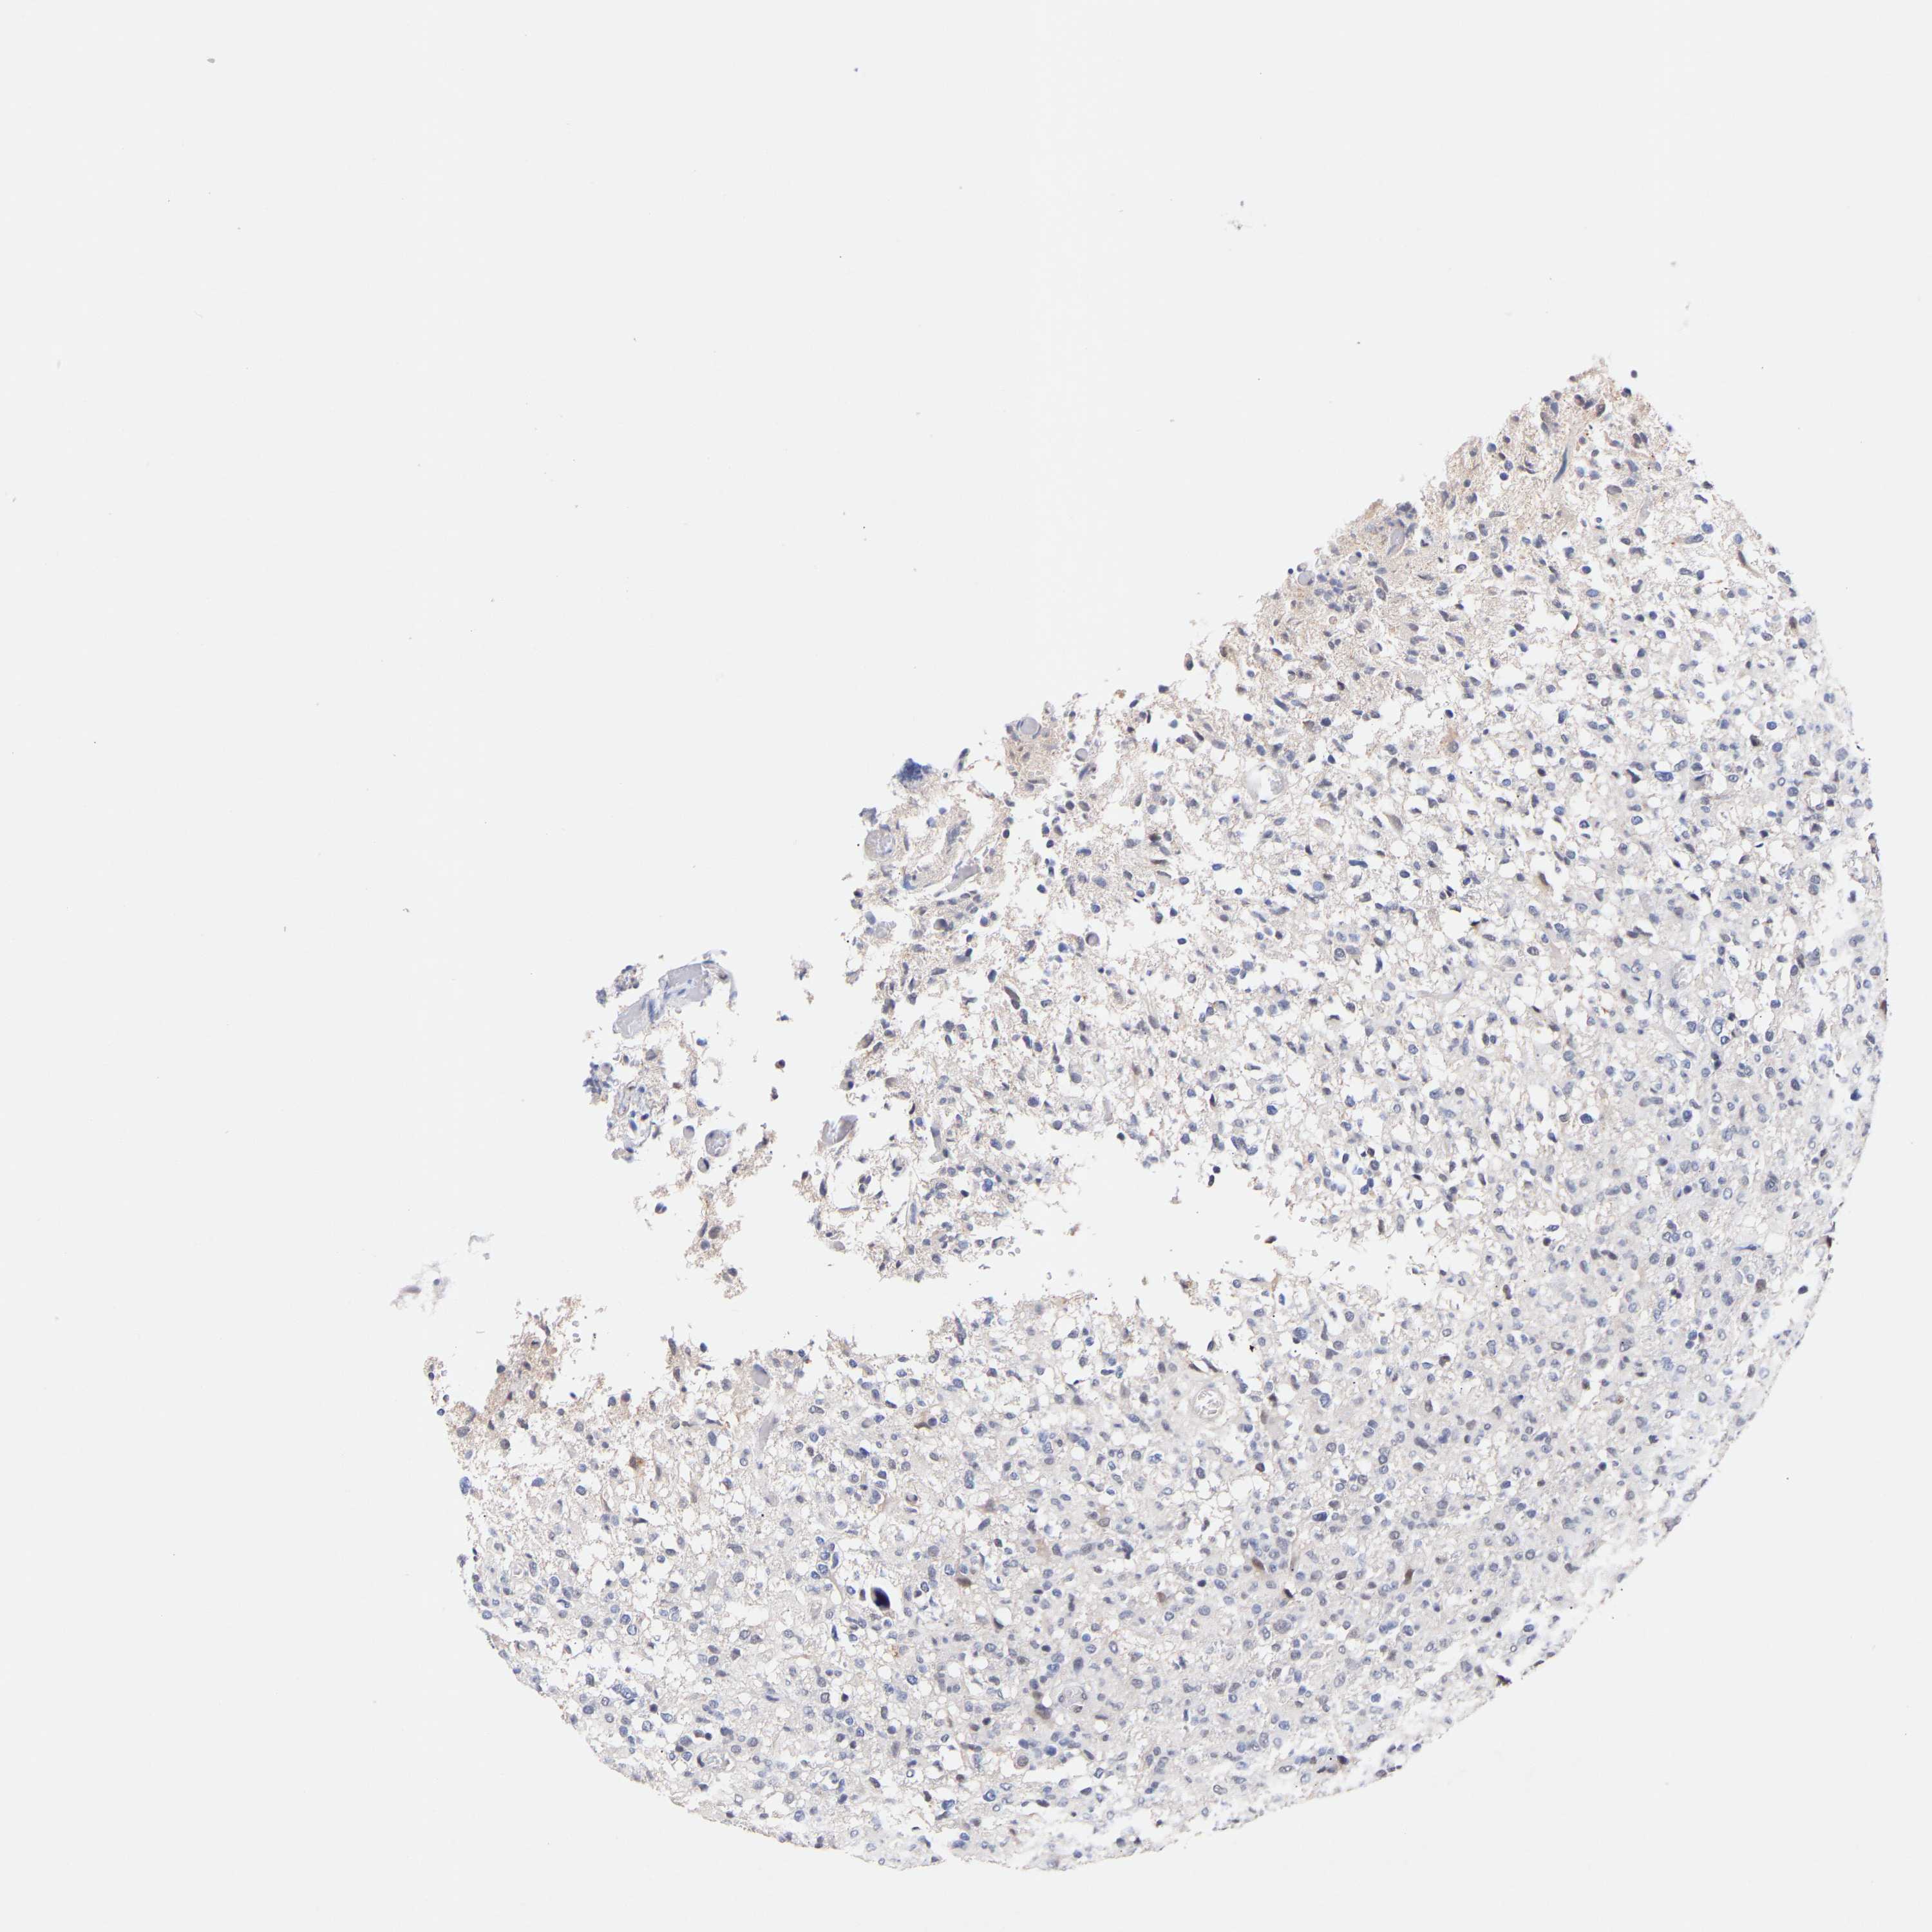

GLIOMA - Protein expressioni

A mouse-over function shows sample information and annotation data. Click on an image to view it in a full screen mode. Samples can be filtered based on level of antibody staining by selecting one or several of the following categories: high, medium, low and not detected. The assay and annotation is described here.

Note that samples used for immunohistochemistry by the Human Protein Atlas do not correspond to samples in the TCGA dataset.

Antibody stainingi

Antibody staining in the annotated cell types in the current human tissue is reported as not detected, low, medium, or high, based on conventional immunohistochemistry profiling in selected tissues. This score is based on the combination of the staining intensity and fraction of stained cells.

Each image is clickable and will lead to virtual microscopy that enables deeper exploration of all samples and also displays staining intensity scores, fraction scores and subcellular localization as well as patient and tissue information for each sample.

Antibody HPA019824

Antibody CAB015201

Staining

High

Medium

Low

Not detected

Intensity

Strong

Moderate

Weak

Negative

Quantity

>75%

75%-25%

<25%

None

Location

Nuclear

Cytoplasmic/membranous

Cytoplasmic/membranous,nuclear

Glioma, malignant, High grade

Glioma, malignant, Low grade